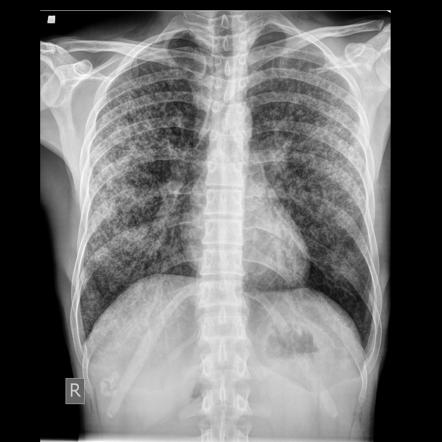

Miliary TB

Miliary TB Haematogenous dissemination

• Diffuse tiny nodules throughout both lungs (miliary pattern).

• May have associated involvement of liver, spleen, brain, etc.